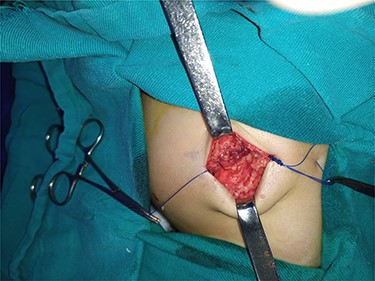

After studying the case, we decided to perform primary repair of the abdominal wall defect without meshplasty since the diameter of the aperture was <5 cm. An oblique left lumbar incision was performed above the hernia, revealing a defect measuring 4 cm in diameter in the upper lumbar triangle. Dissection of the peritoneum and hernial sac was performed starting from the margins of abdominal muscles (Fig. 4), the hernial sac was internally reduced and the muscular margins were closed by simple continuous sutures made from prolene 0 (Fig. 5). Complete closure of the defect was confirmed and a draining tube was inserted subcutaneously before closing the skin. The drain was removed after 2 days; the stitches were removed after 10 days. The patient was faring well after the surgery. Recurrence of the hernia was not reported. We recommended that the patient should be followed up by an orthopedist for the correction of disability, which is caused by LCVS.

The consolidation stage after reduction of the hernia sac of the abdominal cavity.